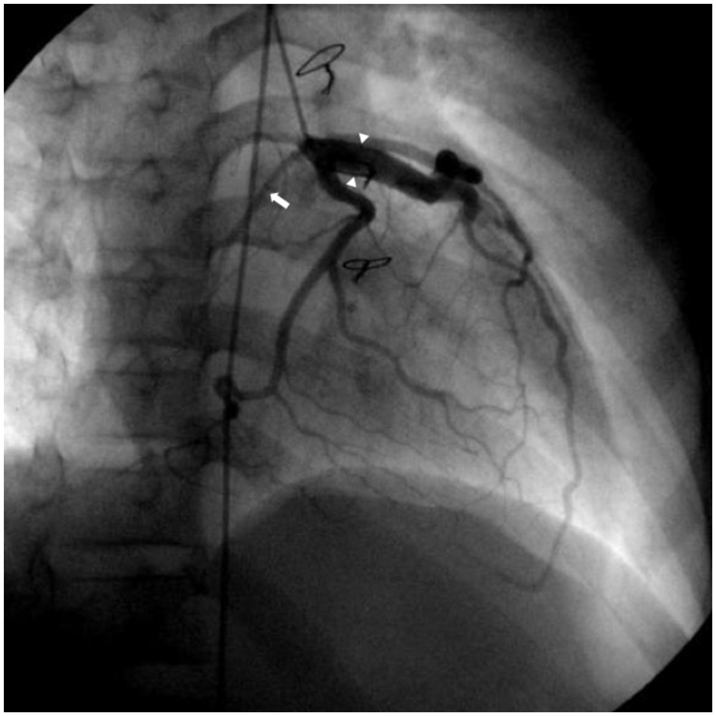

左単一冠動脈の拡張を伴い,SHOC2遺伝子異常が認められたNoonan症候群の1例A Case of Noonan Syndrome with the SHOC2 Mutation Complicated by Dilation of a Single Left Coronary Artery